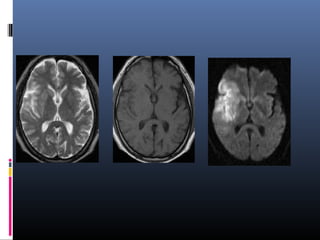

DWI & ADC

Diffusion-weighted MRI

Apparent Diffusion Coefficient

 It is a measure of diffusion

 Calculated by acquiring two or more images with a different gradient

duration and amplitude (b-values)

 To differentiate T2 shine through effects or artifacts from real ischemic

lesions.

 The lower ADC measurements seen with early ischemia,

 An ADC map shows parametric images containing the apparent diffusion

coefficients of diffusion weighted images. Also called diffusion map